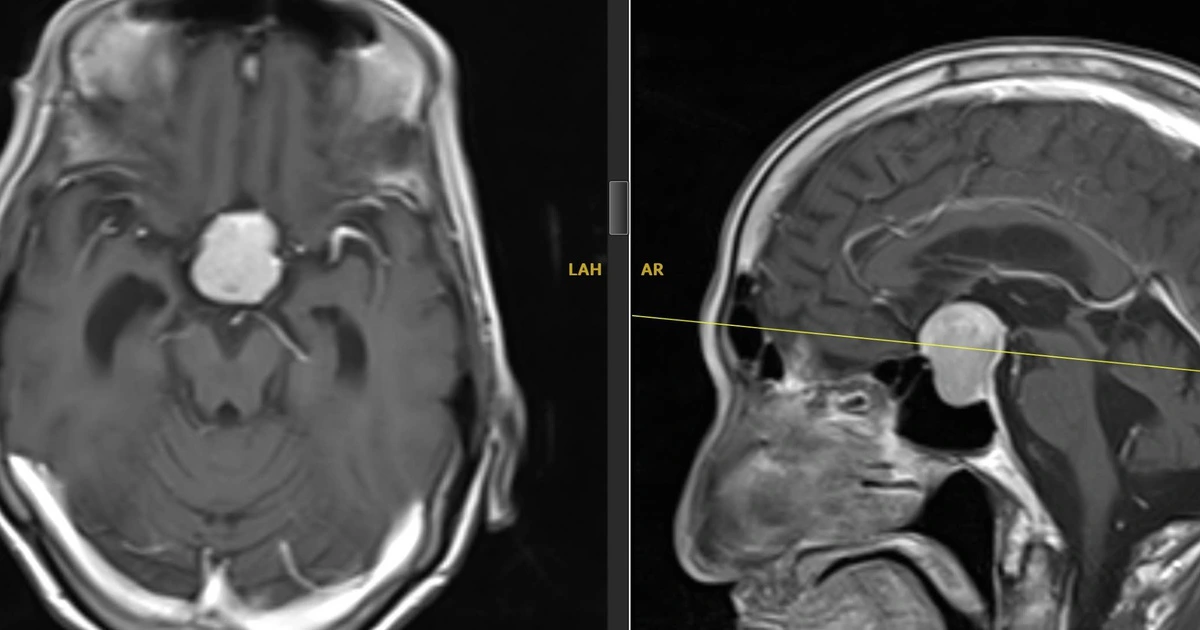

Dựa trên kết quả MRI, các bác sĩ Bệnh viện đa khoa Xuyên Á chẩn đoán bệnh nhân có một khối u tuyến yên kích thước 3 cm gây chèn ép dây thần kinh thị giác. Khối u này cũng là nguyên nhân khiến chị L. mờ mắt, đau đầu thường xuyên. Sau khi hội chẩn, các bác sĩ thống nhất thực hiện ca phẫu thuật nội soi bóc tách lấy khối u, giải phóng dây thần kinh cho người bệnh.

Tương tự bệnh nhân L., ông N.V.H (74 tuổi, Cà Mau) cũng mắc u tuyến yên lớn với kích thước 3,1 cm chèn ép dây thần kinh khiến ông mờ mắt, đau đầu hơn 6 tháng nay. Khi đến Bệnh viện đa khoa Xuyên Á thăm khám, ông được chụp MRI và chẩn đoán u tuyến yên lớn. Với bệnh cảnh này, ông cũng được chỉ định phẫu thuật nội soi loại bỏ khối u.